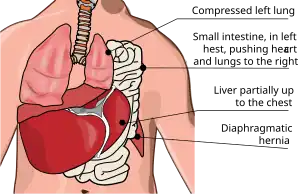

Bochdalek hernia is one of two forms of a congenital diaphragmatic hernia, the other form being Morgagni hernia. It results in an opening in the diaphragm which allows intra-abdominal organs (particularly the stomach and intestines) to enter the thoracic cavity. This generally results in one lung being deformed,[3] and the resulting lung compression can be life-threatening.

Bochdalek hernia can be a life-threatening condition. Approximately 85.3% of newborns born with a Bochdalek hernia are immediately high risk.[8] Infants born with a Bochdalek hernia have a "high mortality rate due to respiratory insufficiency".[9] Between 25 and 60% of infants with a Bochdalek hernia die.[7] The lungs, diaphragm, and digestive system are all forming at the same time, so when a Bochdalek hernia permits the abdominal organs to invade the chest cavity rather than remain under the diaphragm in the correct position, it puts the infant in critical condition. These "foreign bodies" in the chest cavity compress the lungs, impairing their proper development and causing pulmonary hypoplasia.[5] Since the lungs of infants suffering from a Bochdalek hernia have fewer alveoli than normal lungs, Bochdalek hernias are life-threatening conditions due to respiratory distress.[5] Like the lungs, the intestines may also have trouble developing correctly. If the intestines are trapped within the thoracic cavity, then the lungs and intestines may not be receiving the amount of blood they need to stay healthy and function properly.